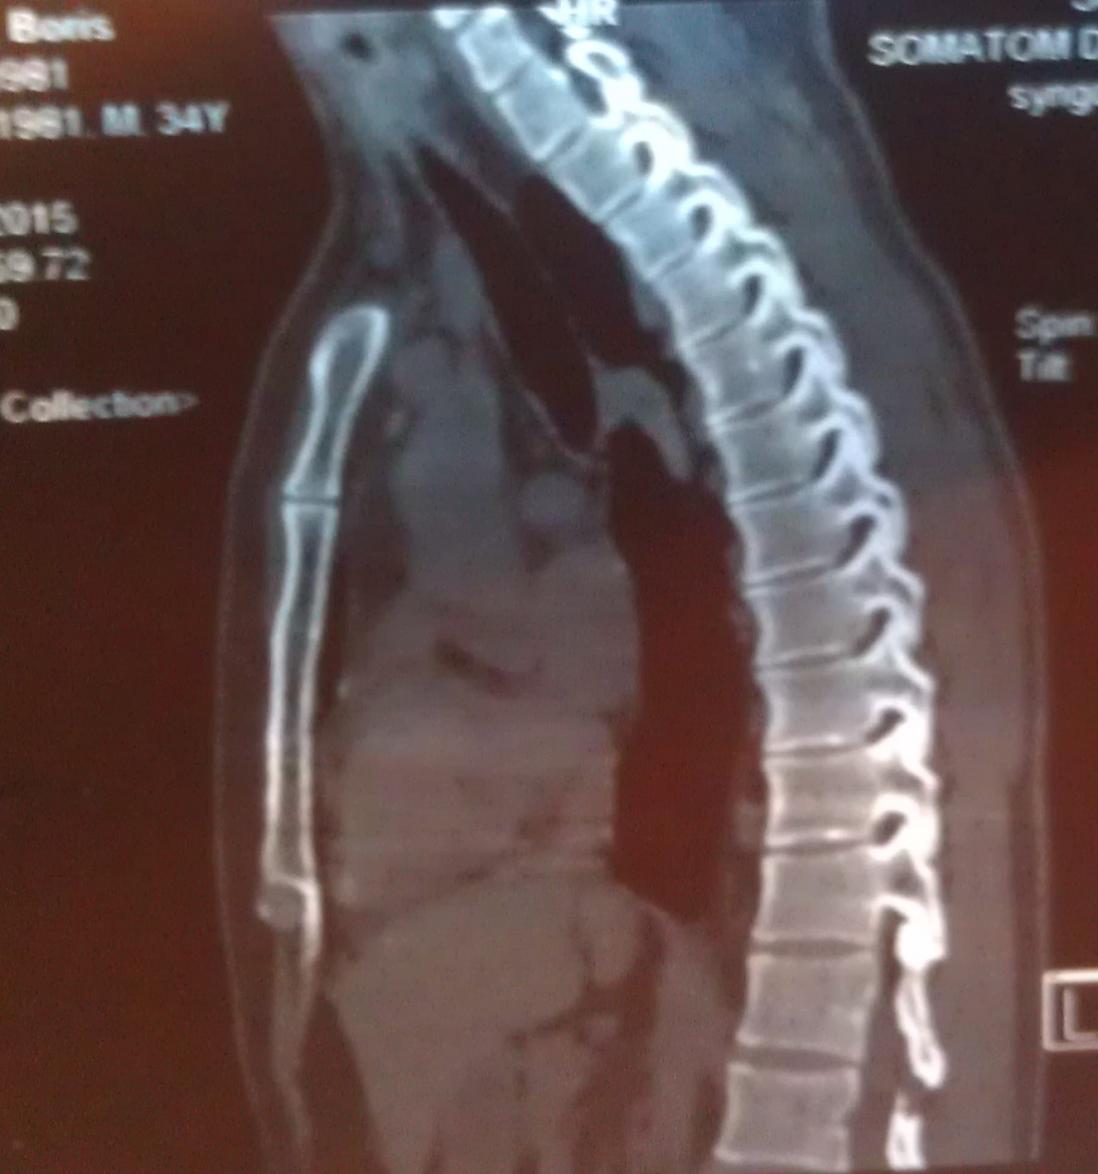

А достаточно ли плохих ревмопроб и компьютерной томограммы, где виден кифоз - чтобы поставить диагноз "болезнь Бехтерева"?

Вот моя компьютерная томограмма позвоночника.

Вложение 1182Вложение 1184Вложение 1185Вложение 1186Вложение 1183